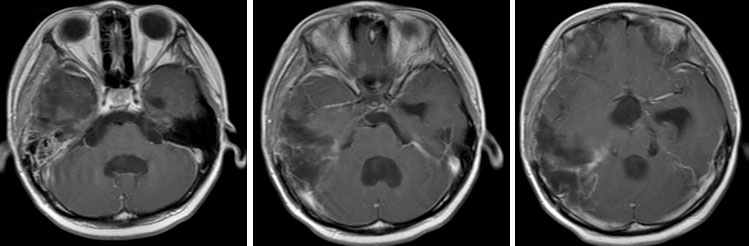

【典型病例】

(2)

放疗前 放疗后

手术全切肿瘤

术后短期内(3周)迅速复发

经过放疗+药物治疗后2月余肿瘤缓解